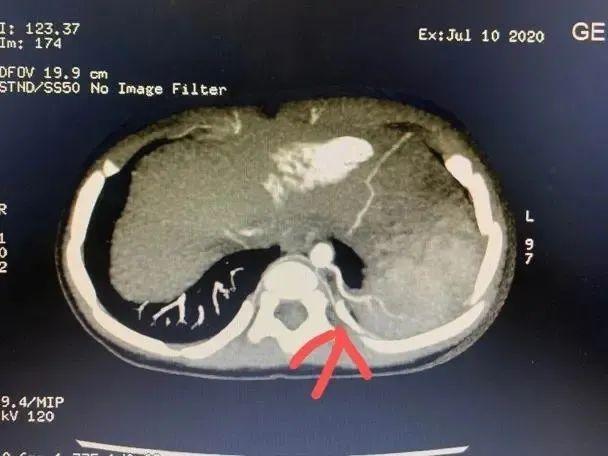

一个咳嗽这么难治愈吗?经过福建省福州儿童医院肺部CT检查,真相是小明的身体里“多了个肺”!!

医学上称为“肺隔离症”。

肺隔离症是一种先天性肺畸形,临床少见,其发病率约占先天性肺畸形的0.15% ~6.45%,一般无明显临床症状,多在合并肺内感染时与正常肺组织相通出现咳嗽、咳痰、咯血等症状,且反复发作,临床易误诊。

●增强CT结合三维血管重建发现异常供血可以确诊